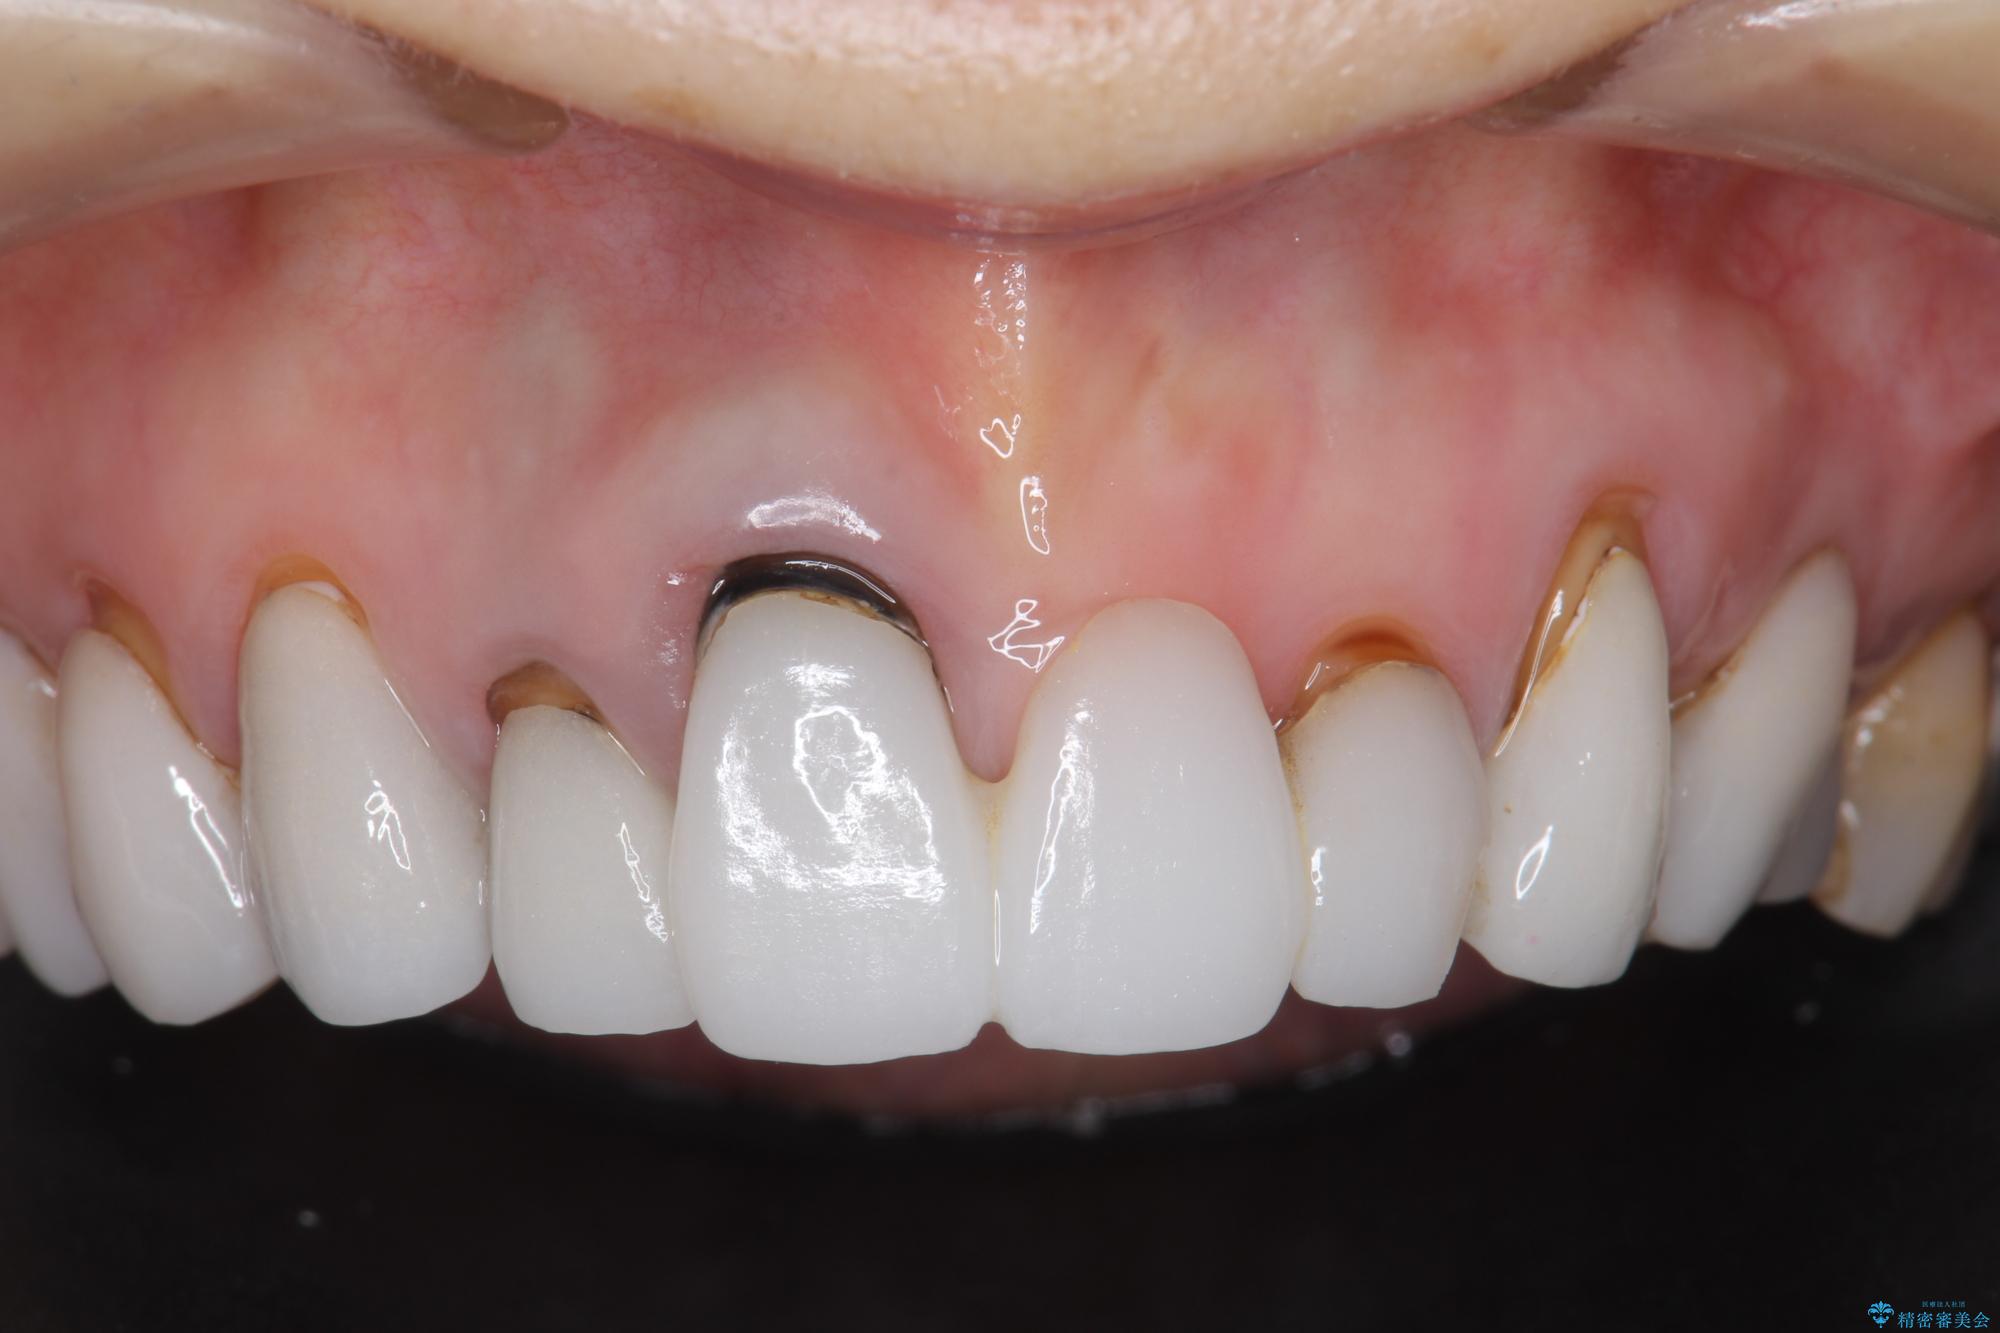

[ セラミック治療 ] 歯ぐきの際の黒ずみを改善したい

- 歯ぐきとセラミックの間の黒ずみが目立つので、きれいに治してほしい。と希望され来院されました。

歯ぐきの位置が変化しクラウン下の歯が見えるようになってしまったことで、審美障害が生じている状態です。

クラウンマージンの再設定を行うことで、黒ずんだ部分を再度覆い、審美障害を改善します。